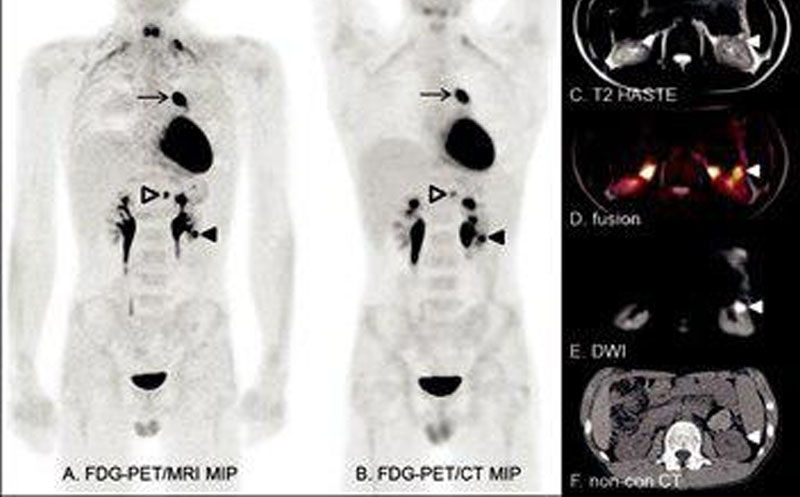

پت اسکن بعد از شیمی درمانی

پت اسکن بعد از شیمی درمانی، یک ابزار بسیار مهم و کاربردی در ارزیابی پاسخ بدن به درمان سرطان است.

چرا پت اسکن بعد از شیمیدرمانی انجام میشود؟

بررسی اثربخشی درمان: مشخص میکند آیا تومور کوچک یا غیرفعال شده است یا نه.

تشخیص بافت زنده سرطانی: پت اسکن میتواند تفاوت پت اسکن میتواند تفاوت بین تودهی مرده (نکروز یا فیبروز) و تومور فعال را نشان دهد.

برنامهریزی درمان بعدی: مثلاً اگر پاسخ ناکافی باشد، نیاز به تغییر دارو یا پرتودرمانی خواهد بود.

شناسایی عود بیماری: پت اسکن در یافتن متاستازهای کوچک یا عود زودهنگام بسیار دقیق است.